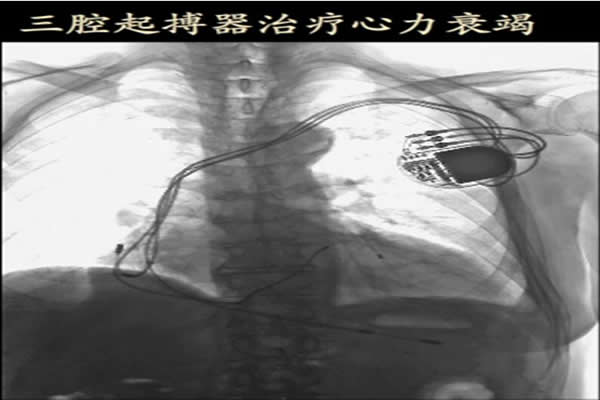

(患者術后的CRT-D影像)

我科46歲的田某患者6年被診斷為“擴張性心肌病、全心衰竭”,反復多次因胸悶、氣短、雙下肢浮腫等不適入住我科,入院后心臟B超檢查示:LVEF(心臟射血分數(shù))為37%,心電圖提示:QRS波寬165ms,24小時動態(tài)心電圖報告:頻發(fā)室性心動過速。雖然已進行規(guī)范的藥物治療,但是治療的效果遠遠不能滿足一個46歲人的生活需求,而且有猝死的危險。為了解決了這一問題,切實提高患者的生存質量,我們科主任徐曉輝、宋宜生以及主管醫(yī)生陳文璐等多人共同討論后,決定為患者實施植入CRT-D的手術治療方案,從而有效地改善心臟功能,減少抗心衰藥物的使用,并大大降低因心肌擴張而導致室速或室顫等潛在并發(fā)癥的發(fā)生。但由于手術費用目前比較昂貴(單起搏器就11萬多),患者遂出院了。出于對我院心內(nèi)科醫(yī)療技術水平的信任,一個月后患者再次入院,要求手術治療。全科的醫(yī)生、護士都非常重視,術前對患者進行了詳細、周密的安排。術中我們嚴格按照流程進行操作,并備好各種應急預案,終于在不到兩個小時的時間里,成功的將帶有除顫功能的三腔起搏器植入患者體內(nèi)。經(jīng)檢測,起搏器各項指數(shù)均正常。術后,在我們?nèi)漆t(yī)護人員的共同精心的照護下康復出院。整個過程得到患者及家屬的大力配合和稱贊。